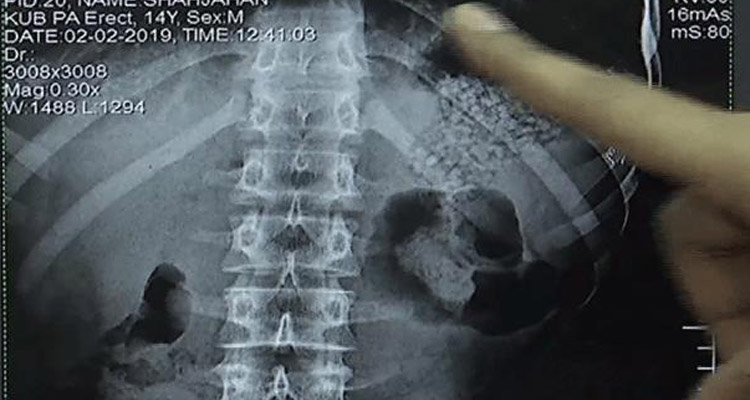

পরে হাসপাতালে নিয়ে এক্সরে করার পর শিশুদের পেটে ইয়াবা থাকার কথা নিশ্চিত করেন চিকিৎসক। দুটি শিশুর পেটে ছোট ছোট ৯৫টি পুটলিতে ছিলো সাড়ে চার হাজার ইয়াবা। চিকিৎসকরা বলছেন, এভাবে পাকস্থলীতে করে ইয়াবা বহনে ক্যানসারের ঝুঁকি রয়েছে।